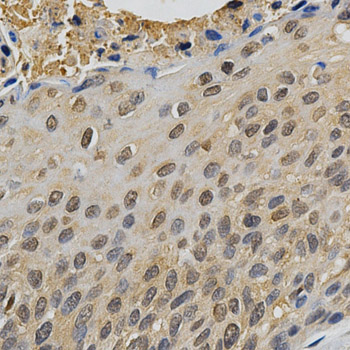

Immunohistochemistry of paraffin-embedded human esophageal cancer using MAPK10 antibody at dilution of 1:200 (x400 lens)